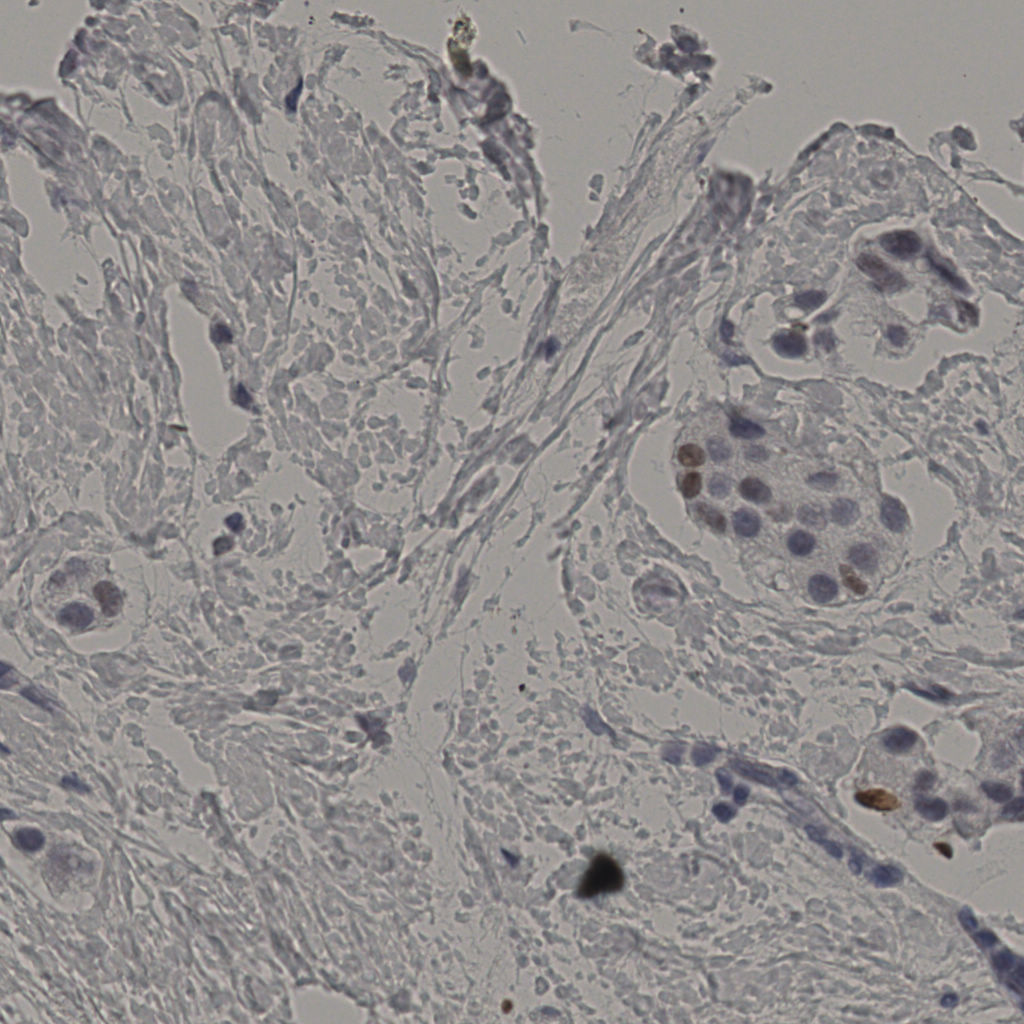

5.31%

Ki67 指数

阴 19502 阳 1093

20240398Ki-67.ndpi

slice_33_9_x29568_y8064.png

slice_33_9_x29568...